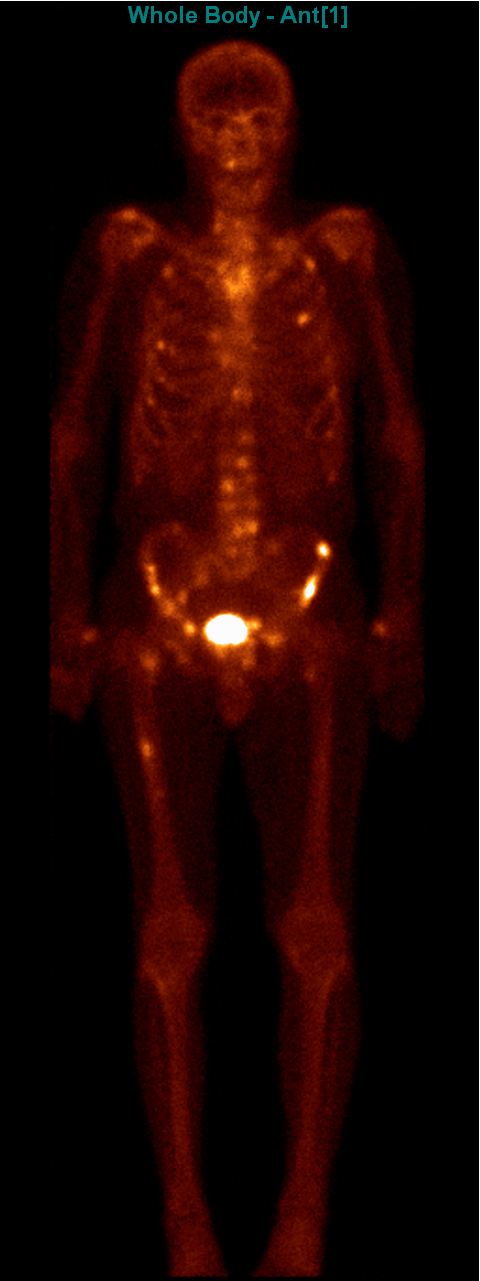

The most common clinical use of FDG-PET is in the form of whole-body scan, with oncologic indications. The majority of malignant tumors operate with higher energy consumption and show an increased glucose metabolism, consequently an increased uptake of FDG. The grade of malignancy is usually proportional to the rate of uptake. This method is useful in oncologic diagnostics, since it is capable to differentiate benign lesions from malignant ones. Whole-body PET imaging is capable to detect the primary tumor with local nodal metastases as well as distant metastatic lesions (staging) in one examination. (Figure 10.)

Test iframe

a

Image

b

c

d

10. Ewing’s sarcoma in the right humerus. Staging FDG PET-CT. PET Maximum Intensity Projection (MIP) image (a), transversal (b,c) and coronal (d) plane fused PET-CT images. Multiplex metastatic process with nodal, lung and bone involvement.